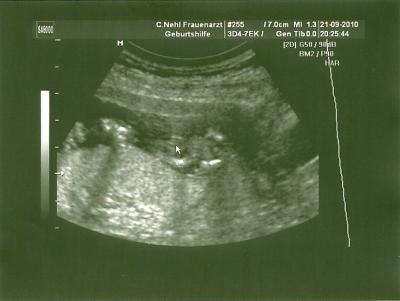

So wir waren ja beim Doch heute. Mussten n bissel warten und dann kam endlich der US dran. Alles ist okay mit dem Würmchen. Haben gesehen wie es getrunken hat, total süß. Muss jetzt in 5 Wochen erst wieder hin, weil sie Urlaub haben. Dann werde ich wohl 3d machen lassen. Kostet 100€ und er macht es über mehrere US Termine. Man bekommt dann später alles auf DVD. Jaaa und dann hab ich natürlich auch gefragt, ob man sehen kann was es wird. Hänge euch mal das Bild an, vielleicht erkennt ihr es ja? LG Steffie

Bild zu Ich war beim FA + Outing - Forum für März - Mamis

Schön, dass alles in Ordnung ist. Schaut ganz stark nach Mädchen aus

Ich hab ehrlich gesagt erst auch nix erkannt. Dann hat der Doc es gezeigt und dann hab auch ich es gesehen. Es wird ein MÄDCHEN Zumindest gestern*hihi* Man weiß ja nie. Aber wenn hier noch einige sind, die ein Mädchen erkennen, hoffe ich mal das es so bleibt. LG Steffie